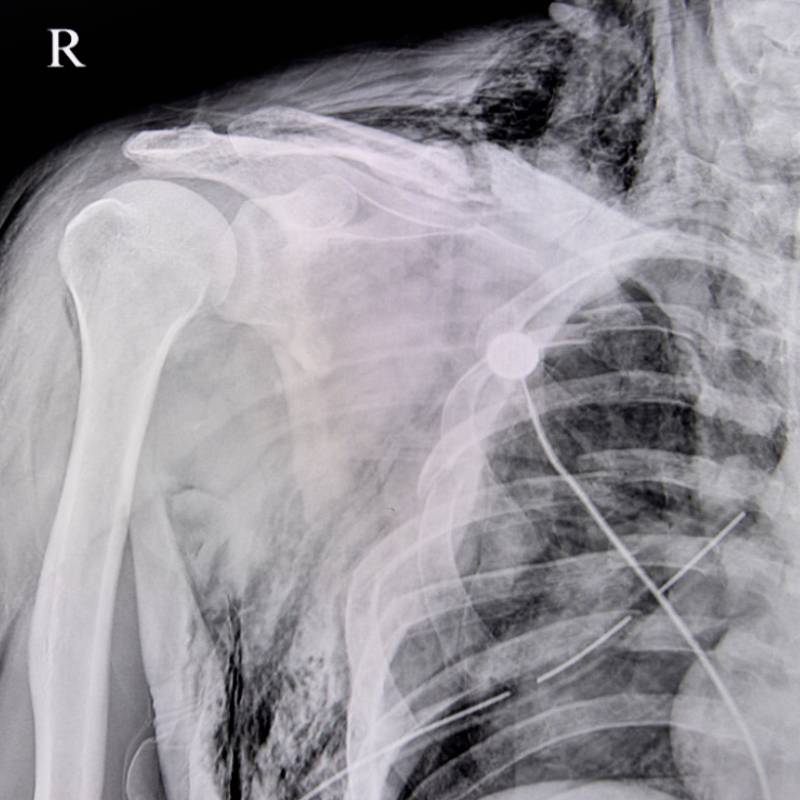

Sinar-X pada bahu untuk melihat kecederaan atau gangguan.